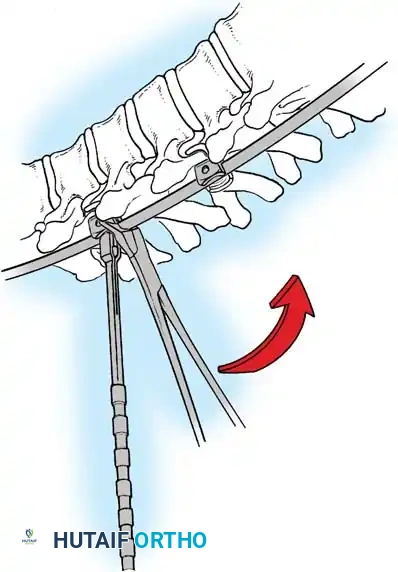

The Hall Technique

The Hall technique offers an alternative method for facet obliteration and grafting, particularly useful in rigid deformities.

Fig. 38-28: The Hall technique of facet fusion, involving sharp excision of the inferior facet and trough creation.

- Sharply amputate the inferior articular facet with a gouge and remove the bone fragment entirely. This exposes the cartilage of the superior facet.

- Remove the exposed cartilage completely with a sharp curet.

- Create a bleeding trough by removing the outer cortex of the superior facet.

- Impact cancellous bone grafts directly into this vascularized trough.

- Complete the procedure with global decortication of the posterior elements.